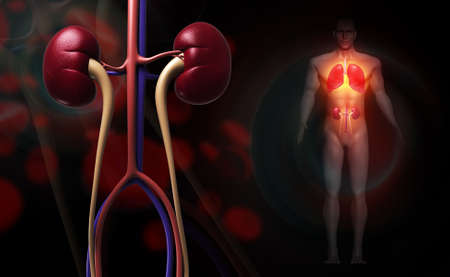

Human male body with highlighted kidneys showing pain and kidney disease. Digital medical concept illustrating internal organ inflammation.

Human male body showing pain in kidneys. Medical illustration of internal organ inflammation, kidney disease, or discomfort.